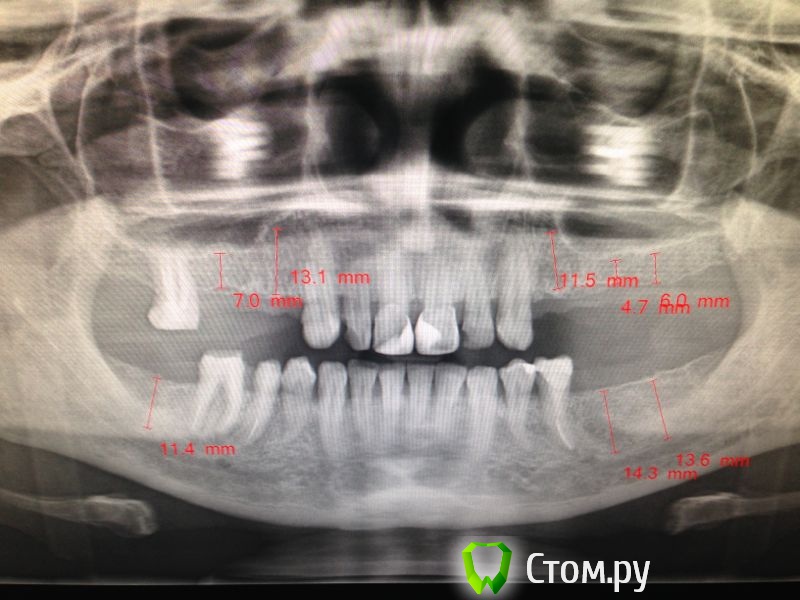

M@estro Опубликовано 28 декабря, 2013 Поделиться Опубликовано 28 декабря, 2013 (изменено) Бруксизм? Пациент сам сказал что скрипит или как. В анамнезе, зубы в/ч удалены причины? Я бы ещё спросил , когда него началось скрежетание зубами. Дело в том,что зубы -то не сильно стёрты судя по орто (и это при отсутствии жевательной группы) . Возможно он скрежетать -то начал недавно из-за миофункциональной перестройки вследствие потери боковой группы. Изменено 28 декабря, 2013 пользователем M@estro 4 Ссылка на комментарий

M@estro Опубликовано 28 декабря, 2013 Поделиться Опубликовано 28 декабря, 2013 (изменено) Бруксизм явление странное, появляется внезапноНу,обычно факторы всё же есть. А здесь мало вводных. Пальпация, привычное смыкание и так далее. И КТ сустава. И когда возникло. И уже думать, почему возникло. А протезирование- 4.6 на выход, 7 имплантатов , коронки на винтовой - и в путь. Пациентка говорит давно зубами скрипит, после обследования ей сказали что от нервов, ранее стояли мосты, но вылетели, может и из-за бруксизма Какие "мосты" ? Как стояли ? Скрипела до "мостов" тоже ? А то может она из-за мостов и бруксила. Изменено 28 декабря, 2013 пользователем M@estro Ссылка на комментарий

diesel87 Опубликовано 28 декабря, 2013 Автор Поделиться Опубликовано 28 декабря, 2013 Как же я далек от этого, думаю наш ортопед не будет этим заморачиваться и поставит дуговые, а хотелось бы конечно на винтах все сделать, с 46 согласен, 35 еще под вопросом. Ссылка на комментарий